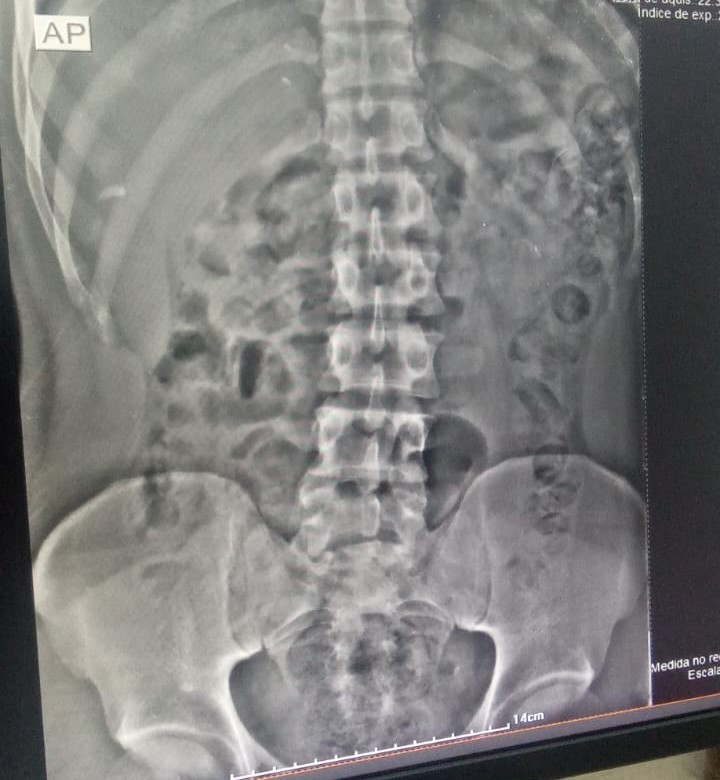

Um mecânico, de 24 anos, tentou entrar na Casa de Prisão Provisória de Formosa, no Entorno do Distrito Federal, com 110 gramas de maconha dentro do estômago, na noite de quinta-feira (4). O homem foi flagrado pelo equipamento de escâner corporal (body scanner), utilizado pelos servidores penitenciários no momento em que ele dava entrada no presídio, com 94 cápsulas.

“Durante sua entrada na CPP, suspeitamos que havia algo errado. Na passagem pelo body scanner, vimos as substâncias ilícitas. Por isso, levamos o preso ao Hospital Regional de Formosa. A tomografia computadorizada sanou nossas dúvidas. Ele passou a madrugada expelindo as cápsulas dentro da cela, separado dos demais apenados”, explica o coordenador da 8ª Regional da Polícia Penal, Ayle Barbosa dos Reis Balbino.